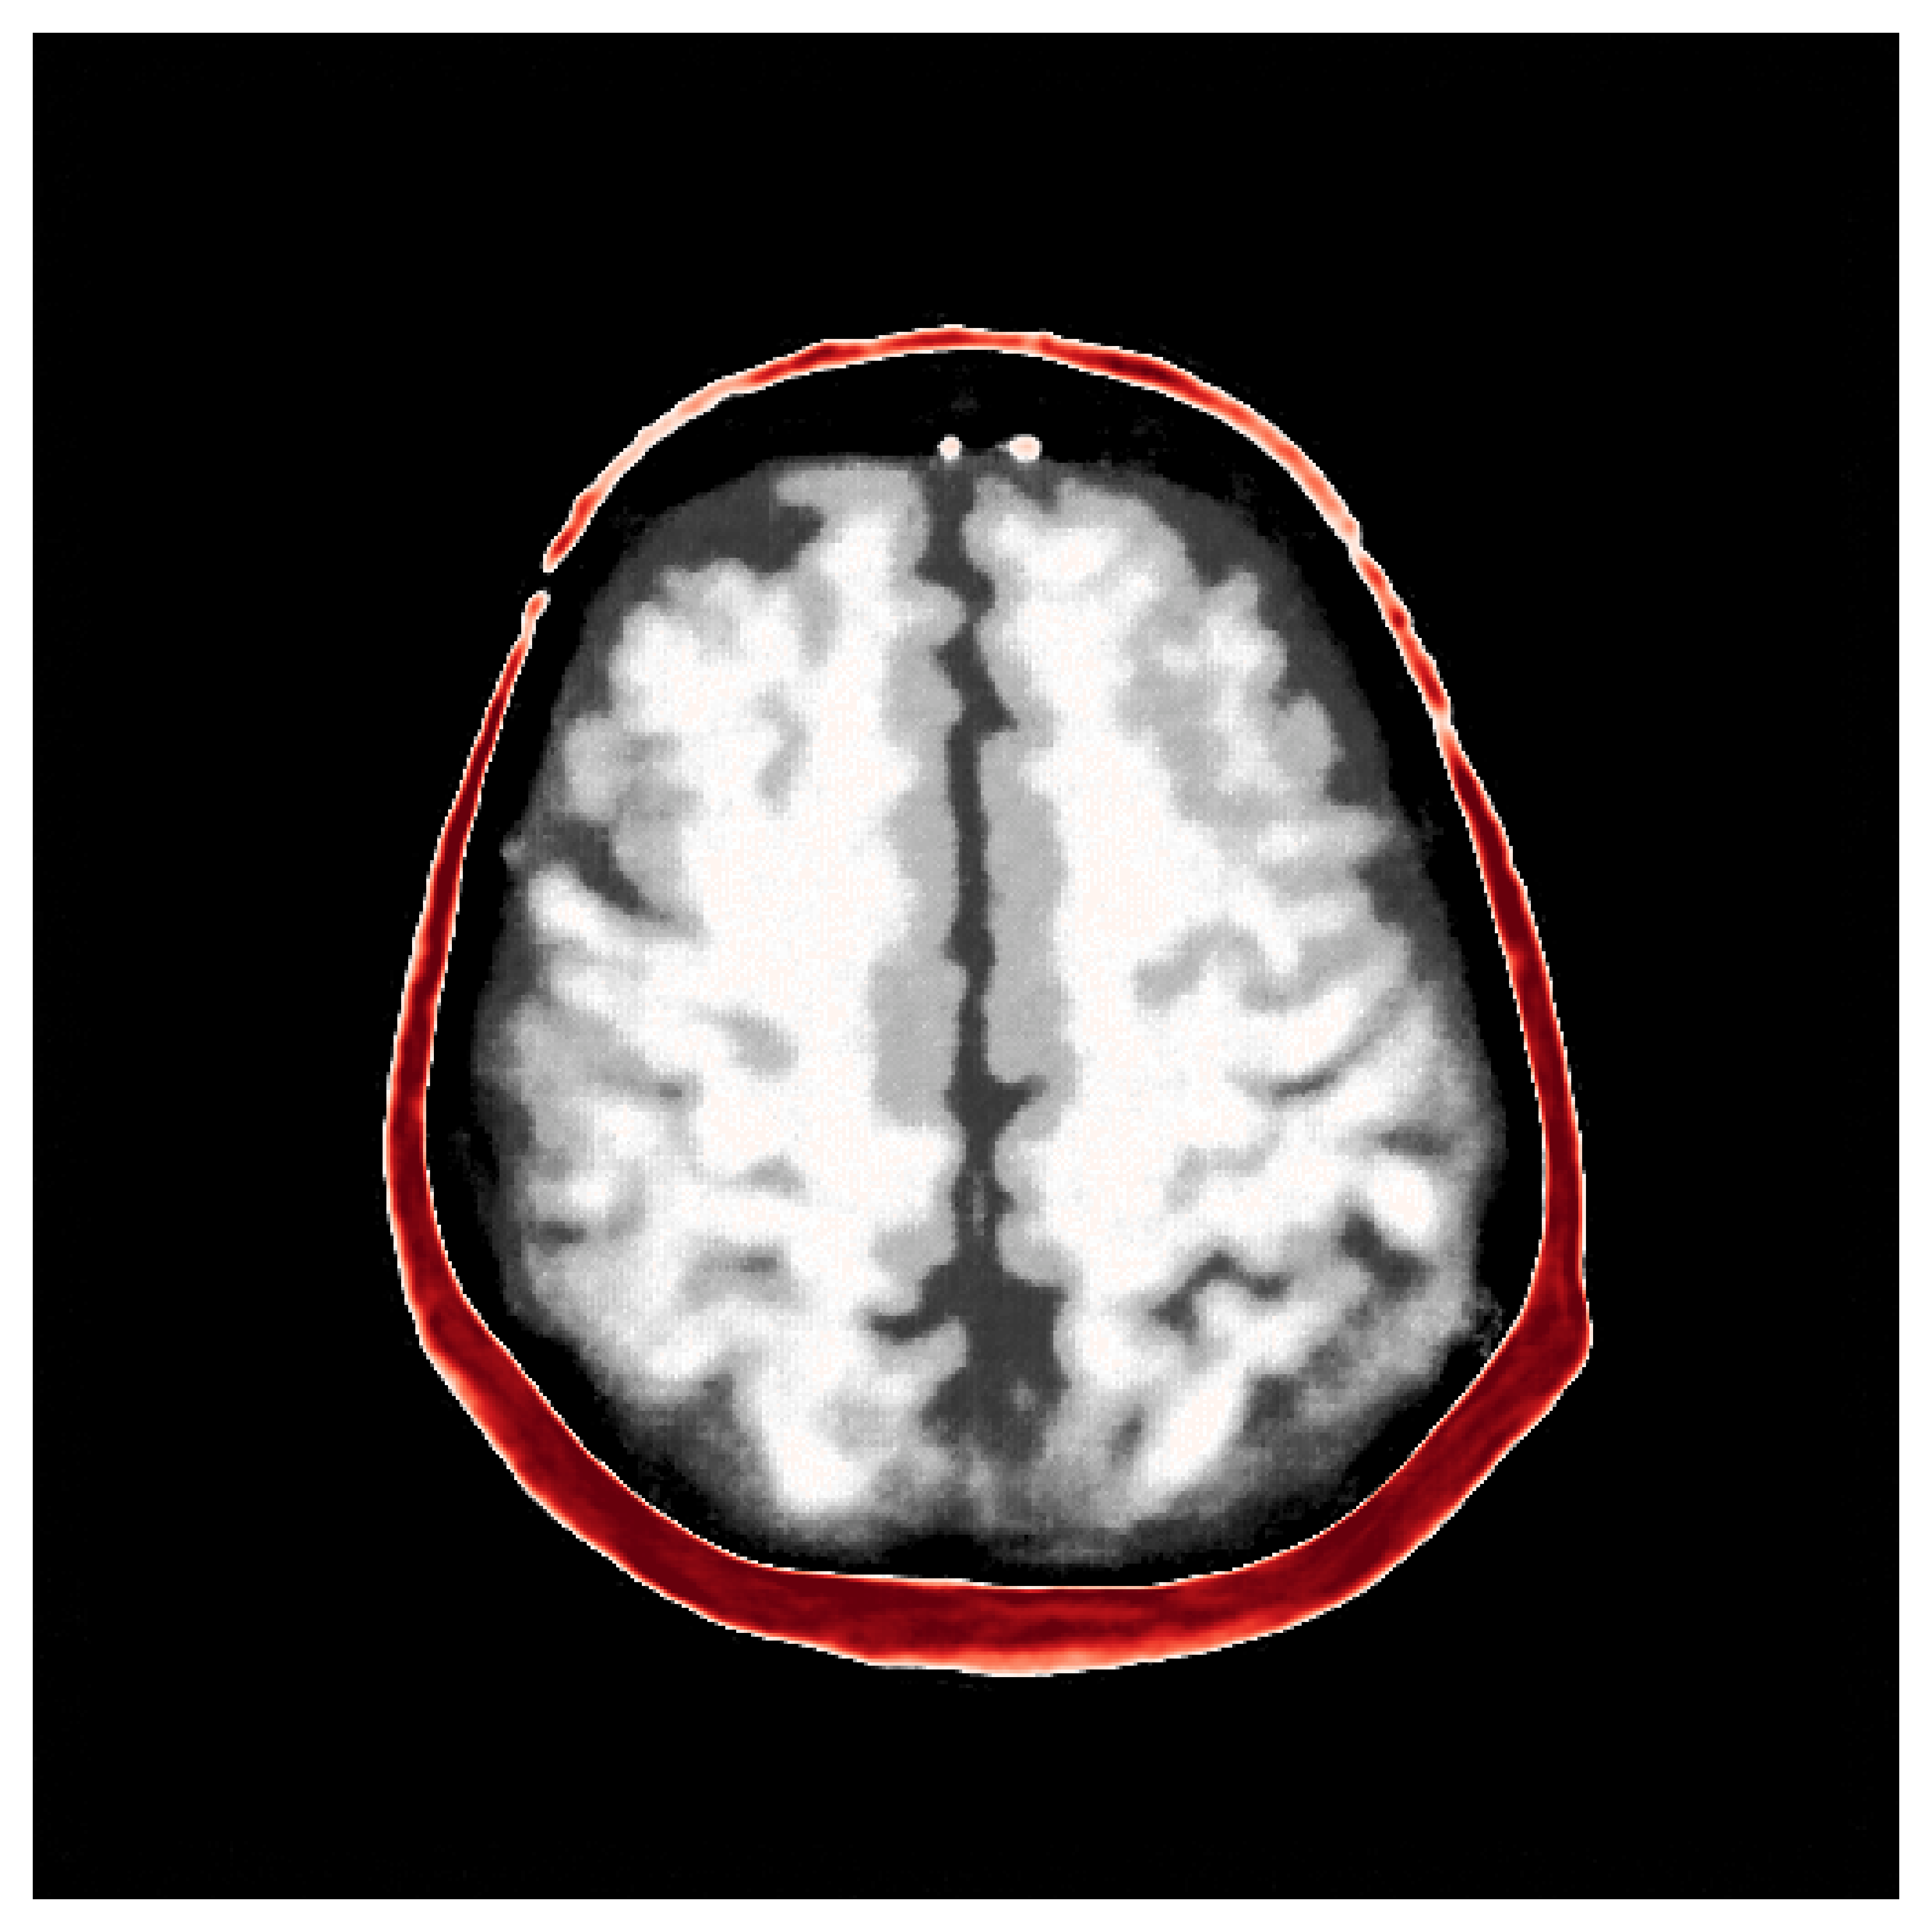

The first step of implementing ASPIRE concerns obtaining samples from a realistic prior for the target parameter vector , in this case, gridded velocity parameters of human brains and skulls. The parameters collected in the MIDA dataset [56] correspond to a single 3D volume for the acoustic velocity collected from a single subject and will unfortunately not be appropriate to train a neural model that will generalize to other human patients. As far as we know, there is no dataset that includes acoustic velocity collected from many patients, so we made our own dataset based off the multi-subject FASTMRI dataset [57]. This custom dataset, detailed in Section \thechapter.A, comprises N=1000 diverse acoustic velocity parameters collected from different human patients, . This size of datasets facilitates generalization of the amortized posterior sampler across different datasets collected from unseen patients. The dataset is accessible via the repo ASPIRE.jl.

Appendix \thechapter.A FASTMRI acoustic dataset creation

Based off of the MRI dataset [57], we manually assigned acoustic values to MRI intensities by following the table of acoustic brain tissue properties in the supplemental section of [47]. Although MRI intensities are not necessarily related to acoustic tissue properties, we found that we could produce reasonably realistic acoustic parameters as compared to the acoustic parameters from the MIDA volume. In Figure 19, we show some example training acoustic parameters. We also plot the average and standard variation between all 1000 training samples in Figure 20. From these plots, we note that there are few similarities between training examples apart from the biologically consistent human brain structures.